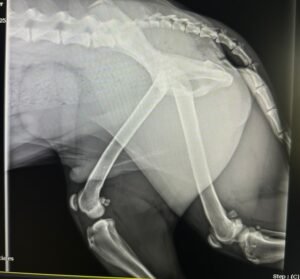

Digital X-rays – Radiographs (X-rays) are usually the diagnostic imaging administered to evaluate your pet. Our office utilizes digital X-rays because they are more accurate and display a higher contrast. Because of their accuracy, technicians are able to take fewer images resulting in less pet discomfort. Digital X-rays also project less radiation than traditional X-rays which improves safety for our staff.

The process for taking radiographs of your pet depends on their temperament and their underlying medical condition. For animals that are calm, we can generally take diagnostic images with minimal manual restraint. We prefer this method for animals that are critically ill and may not handle sedatives well. If your pet is more excitable or in pain, we will generally use sedation to help facilitate quality imaging. Pets must lay very still for the images to be of high quality, so in many cases sedation is necessary.